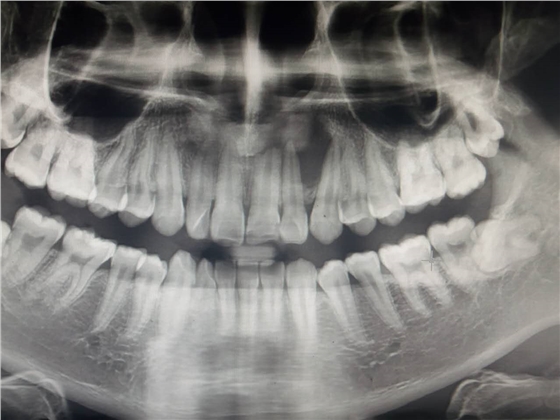

死髓牙2度,沒(méi)保留價(jià)值了,外傷造成的外吸收,即使到充也容易出問(wèn)題。和患者溝通,要求做種植,用了兩個(gè)骨膠原,側(cè)切、尖牙沒(méi)事,側(cè)切做了一次根充